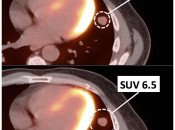

The effects are so significant for small lesions, that lesions less than 8.0-mm should be considered “beneath the resolution of PET”.  [FIG. 4]

Therefore, a 6.0-mm non-avid pulmonary nodule should not be dismissed as benign simply because it is non-avid.  A nodule of this size must be considered “indeterminate”, as it is “beneath the resolution of PET ”.